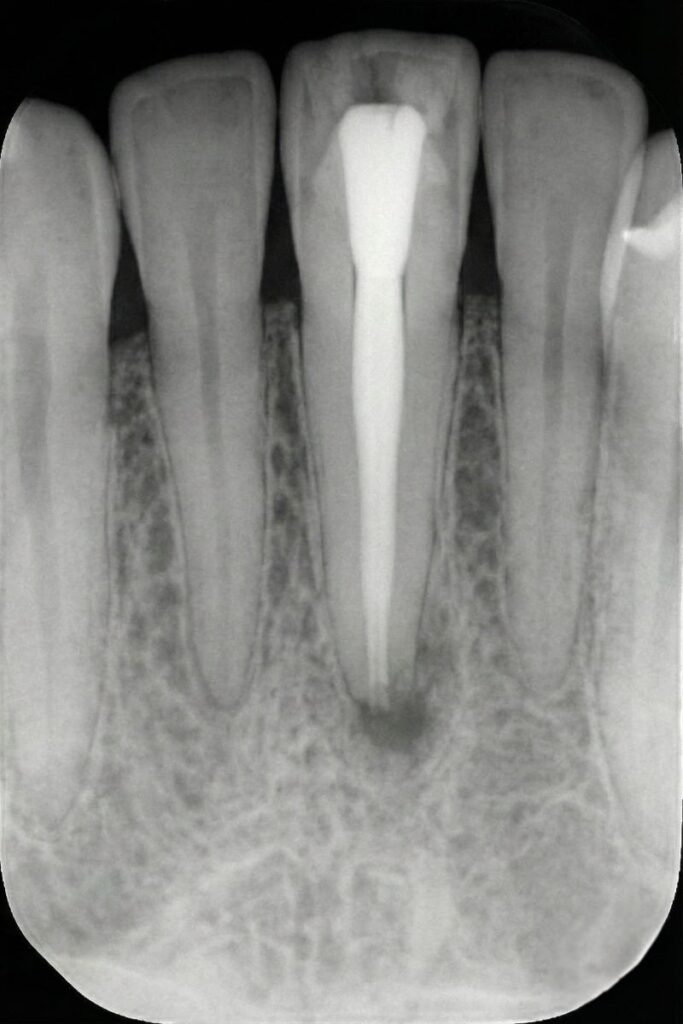

Retreatment of a root canal involves reopening the tooth, removing old gutta-percha and debris, disinfecting the canals and resealing them to eliminate persistent infection. This conservative procedure addresses hidden canals, complex root anatomy or new decay that compromised the original treatment. When standard retreatment is not enough, we may recommend an apicoectomy, which surgically removes the root tip and infected tissue through the gum.

Digital 3‑D imaging, rotary instruments and ultrasonic irrigation help us clean canals thoroughly and perform efficient single‑visit treatments.

When a first root canal doesn’t heal properly, lingering bacteria can cause pain, swelling and bone loss. Retreatment removes old filling material, cleans previously untreated or reinfected canals and reseals the tooth, helping preserve your natural root and avoid extraction or implants.

By keeping the root, you maintain normal chewing forces, jawbone health and proper tooth alignment. Retreatment is often a more conservative and cost-effective option than removing the tooth and replacing it with a bridge or implant. With modern anaesthetic, sedation and rotary instruments, retreatment is typically well tolerated. Many patients compare it to having a filling, and a properly crowned tooth can continue functioning for decades.

A retreatment root canal is performed when a previously treated tooth becomes reinfected or fails to heal. The dentist removes old filling material, cleans the canals again and reseals the tooth to support proper healing.